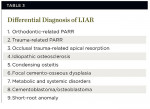

A differential diagnosis would be limited for this entity due to the benign nature and radiologic features of this condition. Possible diagnoses are listed in Table 3.

The most likely diagnoses to exclude would be PARR from orthodontics or trauma. LIAR occurs in the mandibular first molars and mandibular premolars, whereas PARR from orthodontics occurs in the maxillary and mandibular anteriors and/or premolars. Trauma-associated PARR usually involves anterior teeth and exhibits pulp obliteration and ankylosis. A history of trauma or prior orthodontic therapy would also differentiate these conditions.

Apical root resorption from occlusal trauma and idiopathic osteosclerosis exhibit a similar distribution to LIAR.29,48-52 The mandibular first molars and second premolars are frequent sites for both conditions. The radiographic changes in occlusal trauma, however, consist of dense sclerotic opaque bone at the apex of the tooth, which sometimes masks the apical root area, in contrast to PARR in LIAR.29,48 Idiopathic osteosclerosis infrequently produces apical root resorption when the lesion is in contact with the root apex.53 This condition is usually separated from the roots of teeth and may occur anywhere in the jaws.49-52 In addition, the sclerotic masses of idiopathic osteosclerosis on dental radiographs are dissimilar to the finely trabeculated bone in PARR.

Condensing osteitis and focal cemento-osseous dysplasia frequently occur in the posterior mandible.4 Apical root resorption has been reported in isolated cases of condensing osteitis.54 The teeth usually have irreversible pulpitis or necrotic pulps, and the apical changes consist of widened PDL space with an increased zone of radiodensity at the root apex in contrast to LIAR. Focal cemento-osseous dysplasia is distinguished by a radiolucent border with a radiopaque center and predominates in females.4

Metabolic and systemic disturbances—such as hormonal imbalances,12 Paget’s disease of bone,55,56 hyperparathyroidism,25 Gaucher’s disease,40 hypophosphatasia,57 Papillon-Lefevre syndrome,58 hemifacial atrophy,59 renal and liver diseases,26,60 focal dermal hypoplasia (Goltz syndrome),61 familial expansile osteolysis,62 and osteogenesis imperfecta63—may need to be considered. However, these disease processes produce a radiographic pattern similar to MIAR and MICR but should be considered in LIAR. A full-mouth radiographic series or panoramic film would be indicated in suspected cases. CBCT images may be beneficial if available.

Cementoblastoma and osteoblastoma are neoplastic processes of cementum and bone, respectively. Cementoblastoma is usually fused to the roots of the tooth, and osteoblastoma is separated from the root apex. These lesions arise in the mandibular molar and premolar region before 30 years of age. Pain and swelling are frequent, and the roots of the involved tooth/teeth are obscured or resorbed as a result of the neoplastic process.4

Lastly, short-root anomaly (SRA) may occur sporadically but is considered a developmental disorder.64 The roots are undersized upon eruption as opposed to fully developed roots that resorb apically. Also, SRA occurs in the maxillary incisors and premolars and mandibular second premolars and is more common in females.